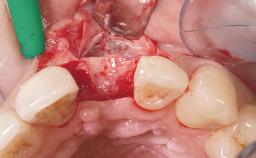

Late Placement of an Implant in a Maxillary Left Central Incisor Site

A 36-year-old female patient was referred for the replacement of the upper left central incisor (tooth 21), which had fractured. Although the tooth had been asymptomatic for many years, the crown began to loosen, at which time she presented to her dentist for an assessment. Teeth 21 and 22 had both been endodontically treated many years previously. She was a healthy individual and a non-smoker.

| Bone Augmentation | Horizontal|Staged |

| Augmentation Materials | Xenogenous|Membrane |

| Soft Tissue Grafting | Simultaneous |